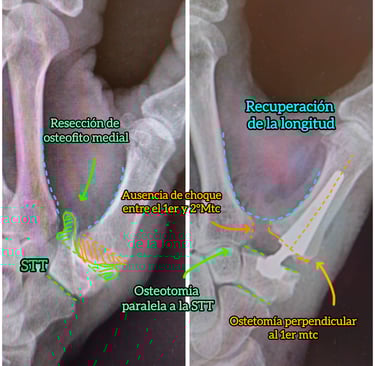

Cirugía percutánea del antepié

Corrección estructural con mínima agresión tisular

✔ Hallux valgus (juanete)

✔ Metatarsalgias

✔ Dedos en garra y martillo

Técnicas: Osteotomías guiadas

➡ Incisiones milimétricas

➡ Menor inflamación

➡ Mejor resultado estético

➡ Deambulación precoz

Reconstrucción biomecánica del pie

Cirugía personalizada en deformidades complejas

✔ Pie plano del adulto

✔ Insuficiencia tibial posterior

✔ Pie cavo

✔ Secuelas neurológicas

➡ Osteotomías estratégicas

➡ Transferencias tendinosas

➡ Restauración del eje mecánico